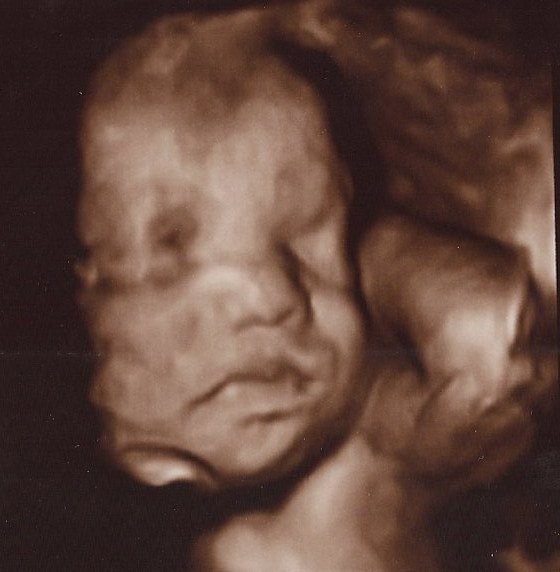

Rose 3D uge 27+ og Rose 1 dag gammel.

Vedhæftede fotos (klik for at se i fuld størrelse)